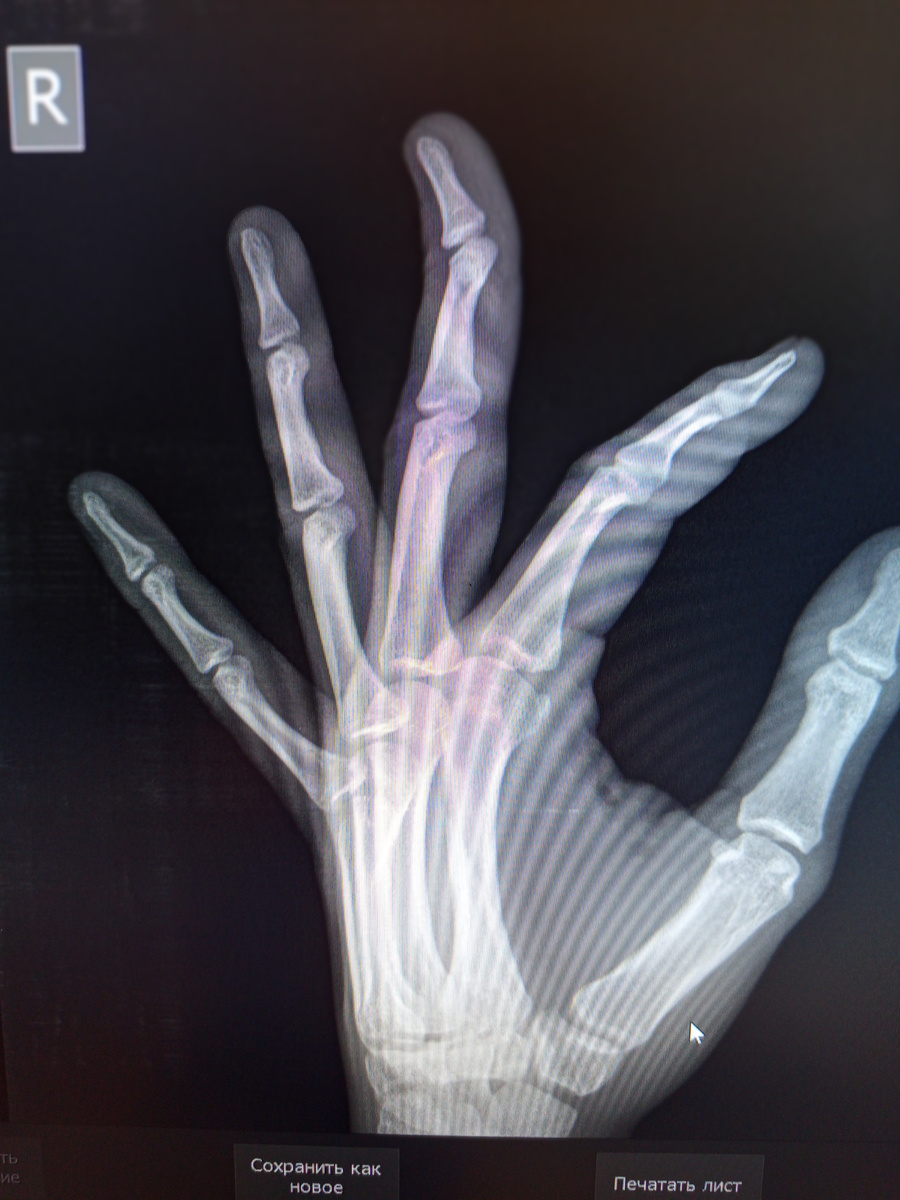

Приемник наполнен людьми и сотрудниками ДПС. Пациент только один , семнадцатилетний парень, остальные сопровождающие.

Ехал на мотоцикле , попал в ДТП, но сильных видимых повреждений нет , но "проходит" по отделению сочетанной травмы.

Назначили кучу снимков, как и положено в таких случаях. Череп , легкие , таз, голень , кисть.

В рубашке парень родился.

Из всего –только палец чуть вывихнут.

Третий палец.